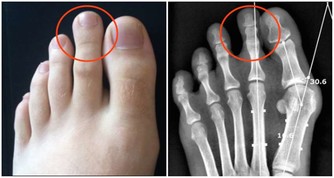

但這個藥有個很大的毒副作用,就是損傷腎臟,像氨基糖甙類抗生素一樣,引起腎小管壞死。

但最近卻一連發現有3位患者,在進行到第4個療程的時候,出現了不同程度的腎功能受損。

當然,我們首先想到的是順鉑對腎臟的損傷,但這幾個病人的腎臟代償能力怎麼就這麼差呢?

帶著這個問題,我在隨訪中對這幾個病人的飲食習慣問了一下,發現她們的確都和我一樣,喜歡吃蘑菇。